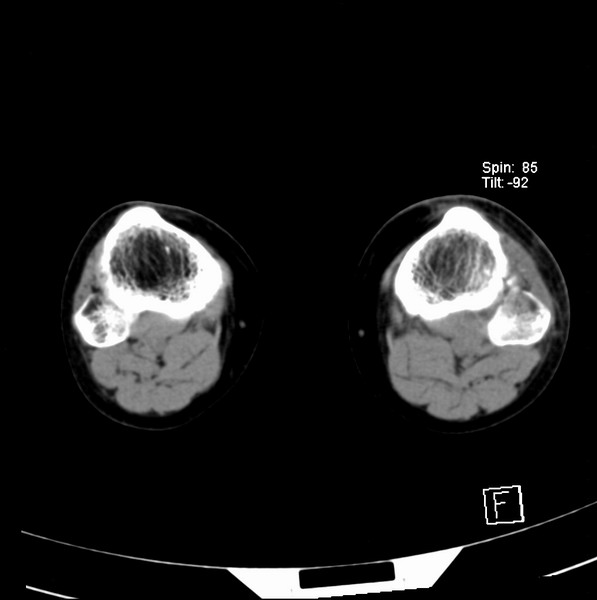

标题: CT21917:右腓骨小头是否骨软骨瘤? [打印本页]

标题: CT21917:右腓骨小头是否骨软骨瘤?

女、43.

不是骨软骨瘤,“牵拽征”,正常变异。有平片吗?

正常变异,“牵拽征”,比目鱼肌牵拽.